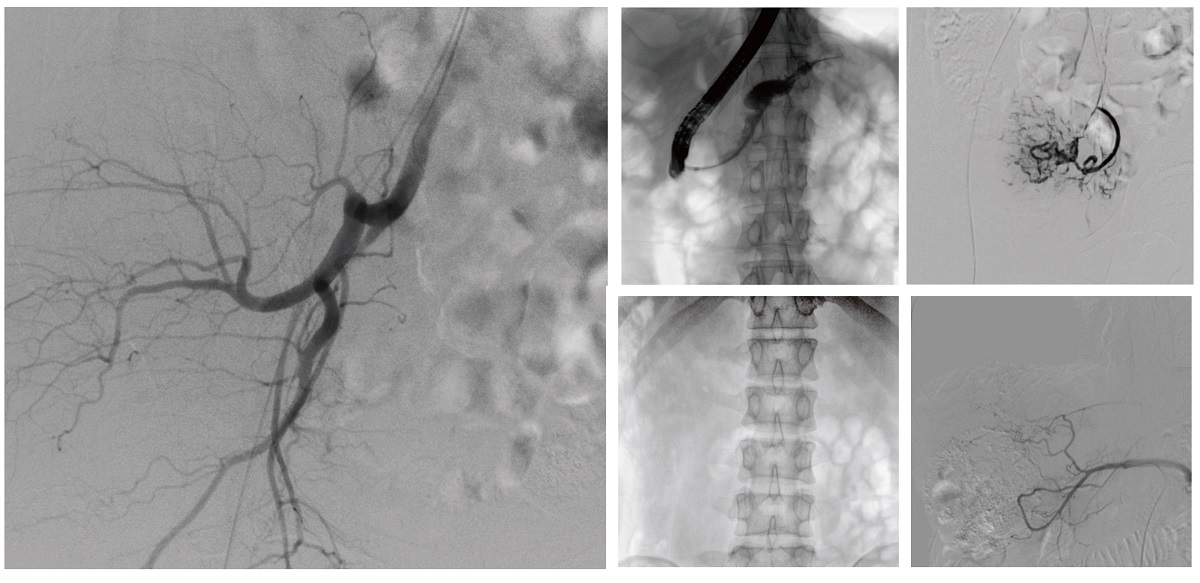

醫院引進(jìn)的普愛(ài)醫療移動(dòng)式平板介入中C,其高清成像能力覆蓋骨科、介入科、泌尿外科、婦產(chǎn)科等多科室,能夠滿(mǎn)足介入微創(chuàng )手術(shù)的多樣化需求。

設備的移動(dòng)式設計,無(wú)需對現有手術(shù)室進(jìn)行改造,適合高負荷手術(shù)量或應急情況下的靈活部署。如在急診介入手術(shù)中,該設備能迅速響應需求,為醫生提供實(shí)時(shí)影像支持,提升搶救效率。